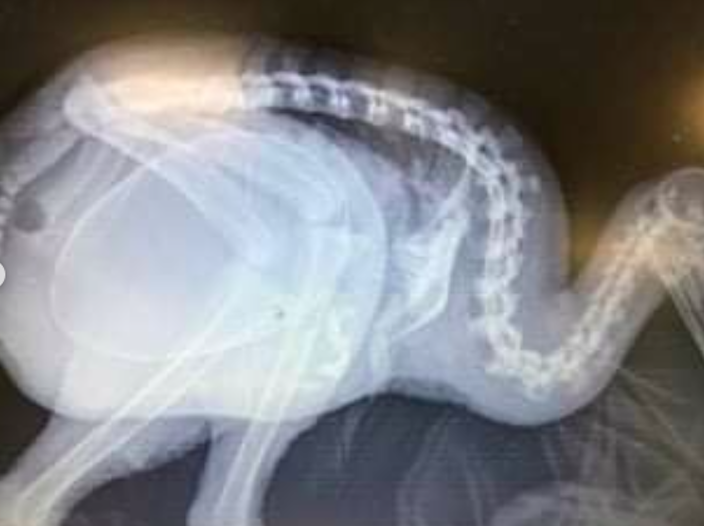

“Wildbase [Hospital at Massey University] vets operated to remove an infertile egg that had become stuck and unable to be passed naturally,” the centre said in a statement. “More surgery was then required to remove her oviduct and most of her left ovary. The surgeries went well but were not enough to save the ailing kiwi whose health continued to deteriorate in the weeks following the operation.”